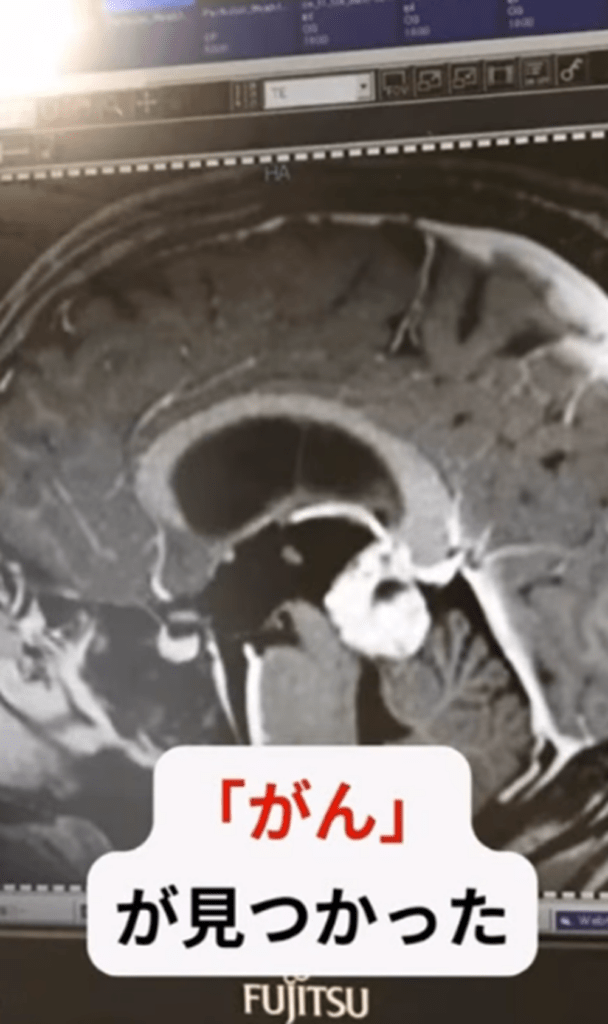

がんと診断(@cancerfighter.rjさんより提供)

3人子を育てるシンママ。しかし「子どもたちをどうしよう」突如判明した病と、現在の様子に迫る